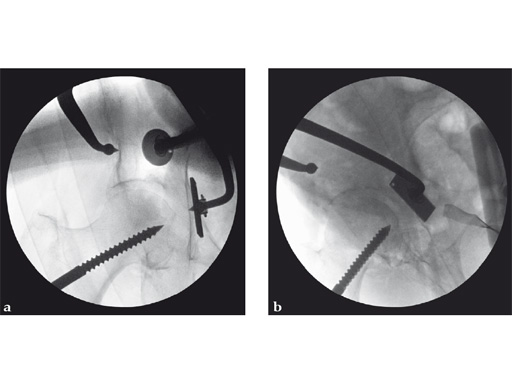

Fig 3ab AP hip and iliac oblique image intensifier views show initial quadrilateral surface plate placement with the aid of an asymmetrical clamp and subsequent introduction of overlying pelvic brim reconstruction plate. In this case a locking pelvic brim plate was chosen because of the severe osteoporosis.